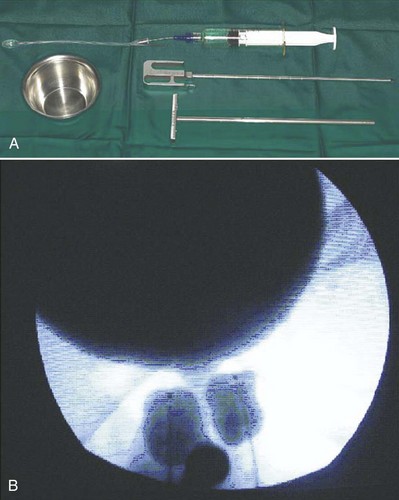

Because of its high viscosity, silicone microimplant (Macroplastique; Uroplasty, Inc, Minnetonka, MN) injections require the use of a ratcheted injection gun (Fig. 74–6A). The injection needle is 7 Fr with a 10-mm, 18-gauge needle tip.

Figure 74–6 A, Silicone macroparticle injection gun. The injection needle is 7 Fr with a 10-mm, 18-gauge needle tip. B, The implantation procedure. The bulking agent is injected through the device using the injection gun and a rigid needle.

(From Tamanini JT, D’Ancona CA, Netto NR Jr. Treatment of intrinsic sphincter deficiency using the Macroplastique Implantation System: two-year follow-up. J Endourol 2004;18[9]:906–11.)

A handheld device that allows the operator to inject Macroplastique transurethrally without cystoscopy was introduced by Henalla and colleagues (2000) in a multicenter trial of 40 patients (see Fig. 74–6B). Device efficacy and acceptability were rated highly by the surgeons at 92.5% and 95%, respectively, and at 3 months 74.3% of patients had a good outcome. Twelve-month outcomes in a cohort of 21 patients who had Macroplastique injections administered with this device were reported by Tamanini and coworkers (2003): 57.1% of patients considered themselves cured, 19% were improved, and 23.8% experienced failure. Outcomes at 2 years showed some deterioration in results, with 47% considered cured, 14.3% improved, and 38.1% failed (Tamanini et al, 2004).